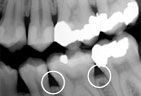

Gum disease is usually caused by plaque, a sticky film of bacteria that constantly forms on teeth. If plaque is not removed with thorough daily brushing and cleaning between teeth, gums become irritated and inflamed. The irritated gum tissue can separate from the teeth and form spaces called pockets. Bacteria move into the pockets where they continue to promote irritation. Left untreated, the process can continue until the bone and other tooth-supporting tissues are destroyed. The early stage of periodontal disease is called gingivitis. It often results in gums that are red and swollen and may bleed easily.

Periodontitis Periodontitis